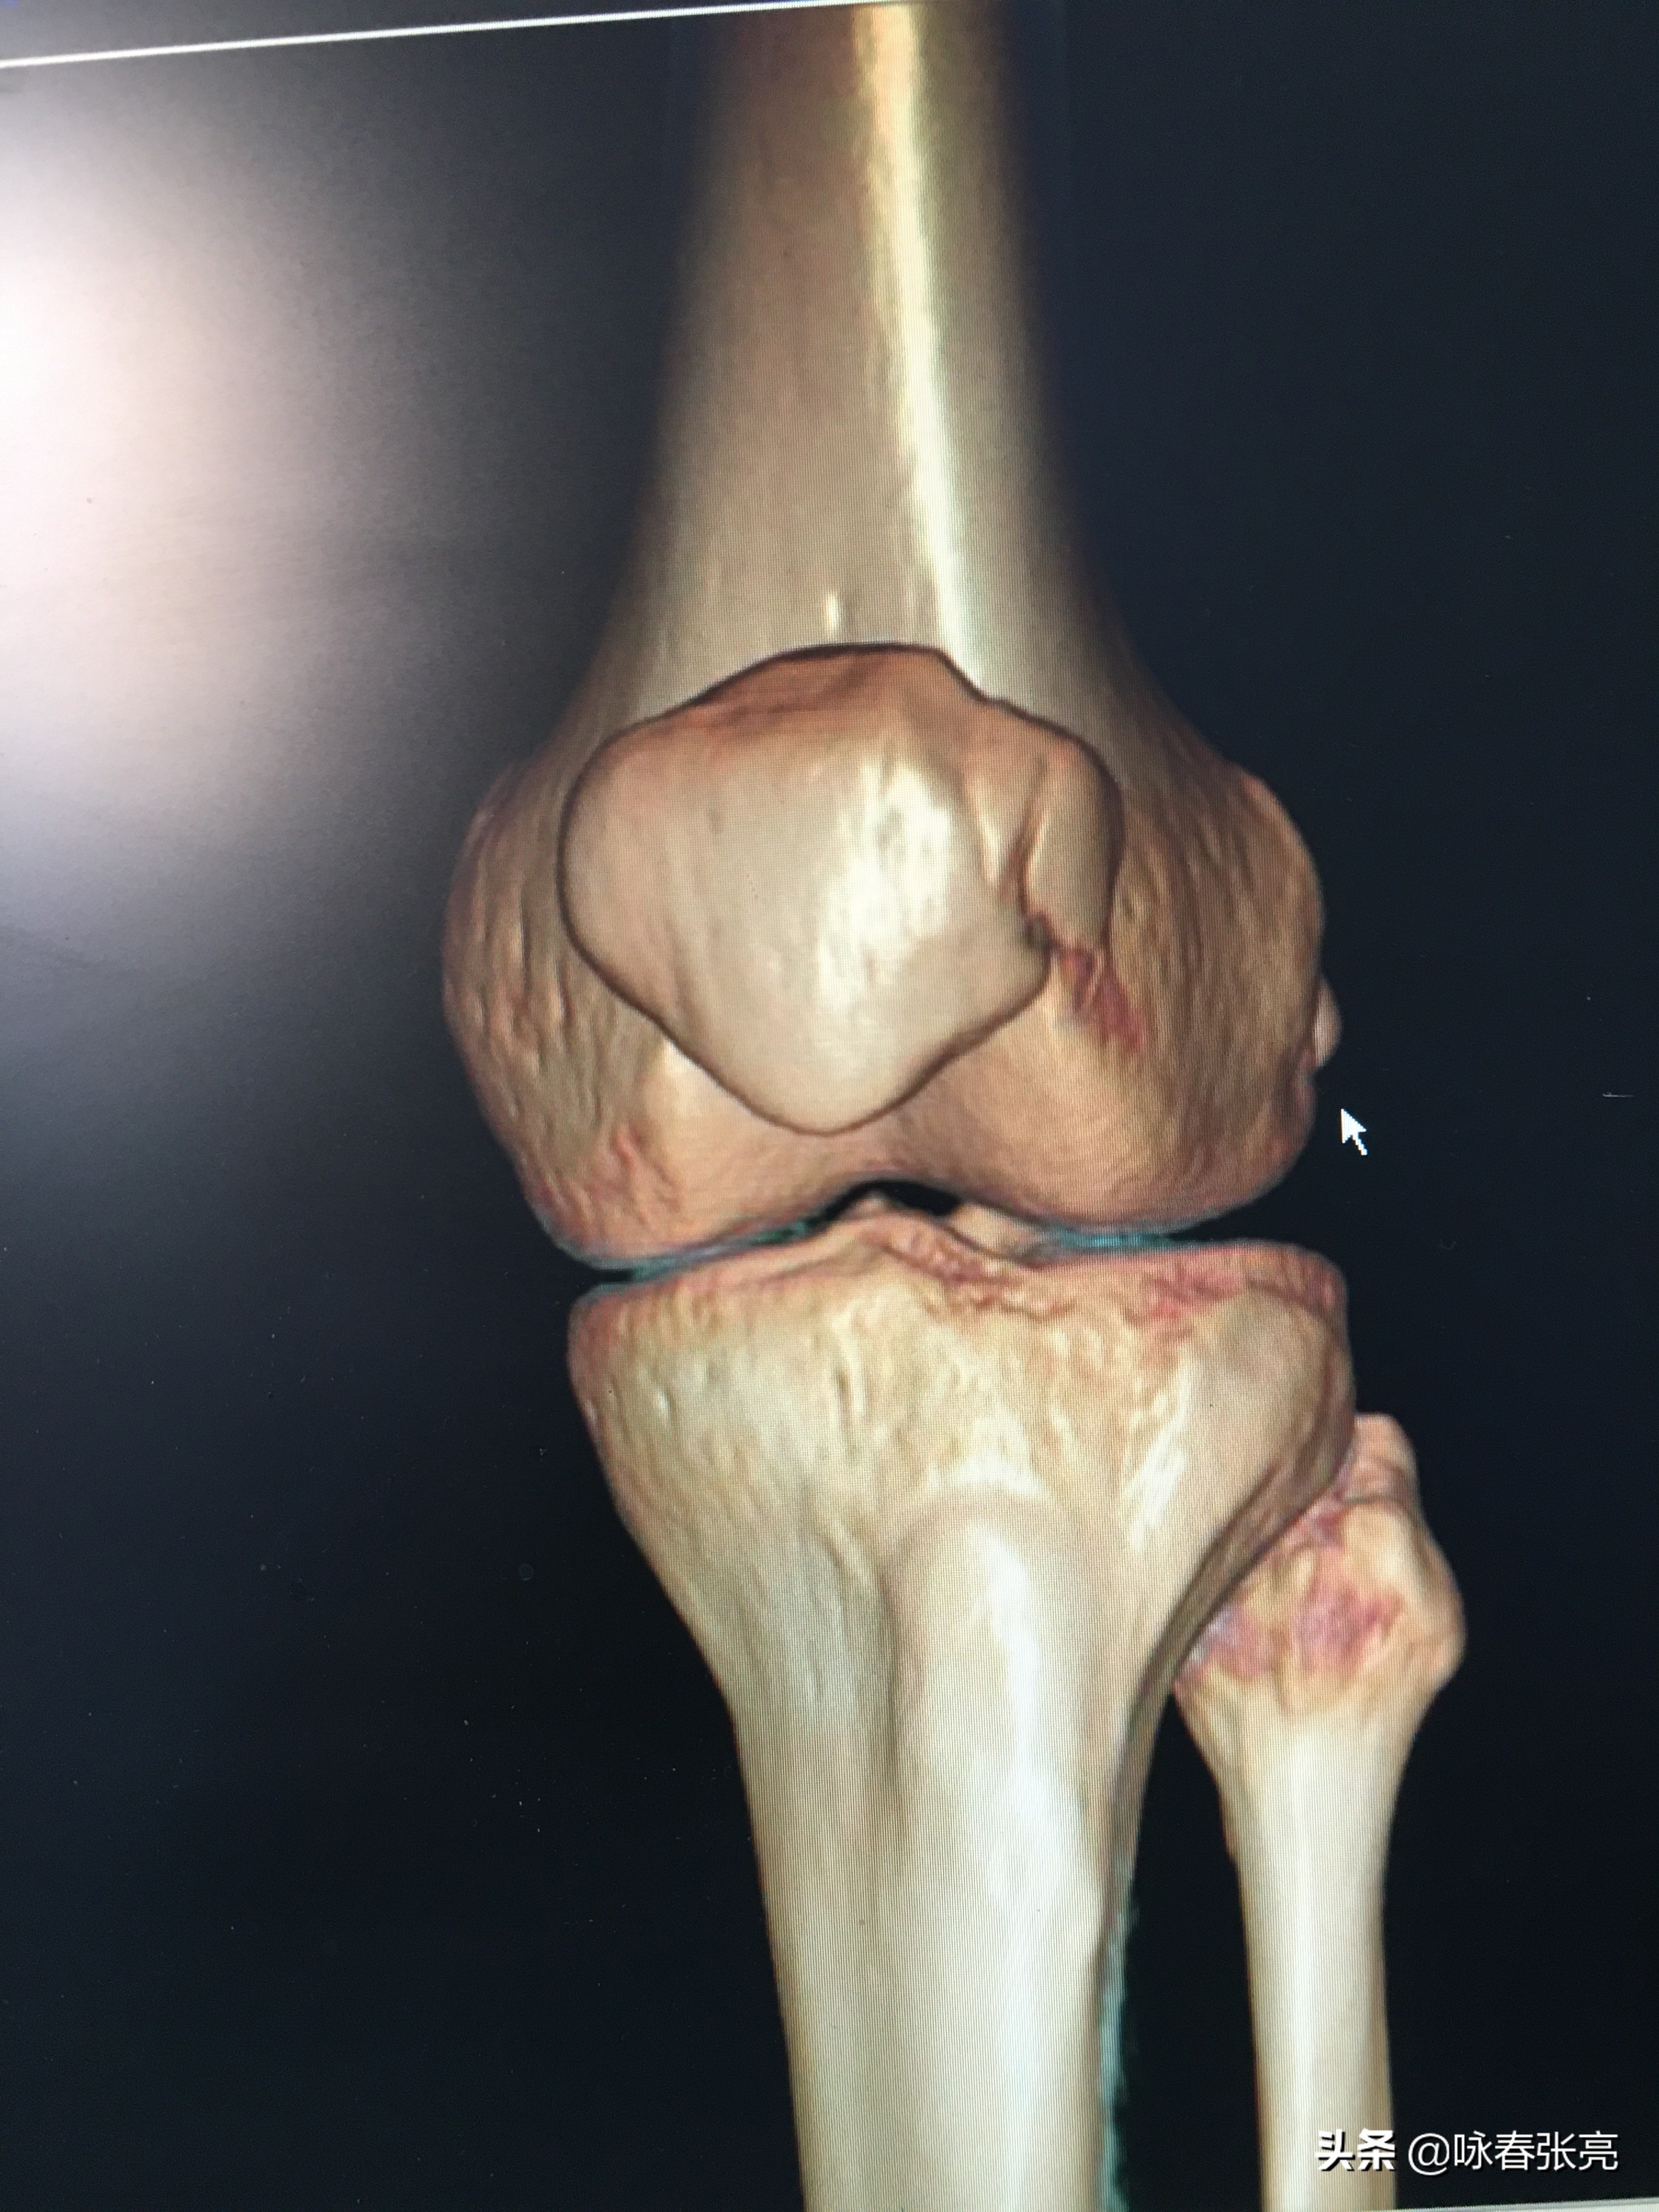

膝关节正面观